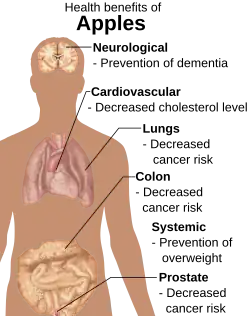

What goes into our bodies is important at any age for various health outcomes but the link to Alzheimer's seems less obvious. Oxidative damage, identified earlier, is affected by diet because a diet rich in antioxidants can prevent much of it (Cotman, 2009). A study done by Dr Cotman (2009) on aged beagles found that an antioxidant-rich diet improved learning, ability to remember and rejuvenated the brain to the point that the dogs could perform tasks that other untreated dogs of the same age could not; they had in fact gained function. This is a very important finding as in humans it could return function to those who have lost it and greatly improve quality of life by rejuvenating the aged brain. Earlier in life the diet can prevent damage from occurring at all or at least reduce it.

A diet that is generally healthy and keeps the body fit and healthy is the best for all life outcomes. Plenty of fruits and vegetables is key as well as low salt, fat and sugar foods that can lead to all kinds of health problems, which often become comorbid with AD (Fillit, et al., 2002). Fruits and vegetables are the best source of antioxidants, with the highest being blueberries and prunes. All have different types which work together to minimise damage and increase repair so the wider variety the better. Also, it needs to be the real thing not supplements as they do not have the same beneficial effects (Cotman, 2009; Deweerdt, 2011).